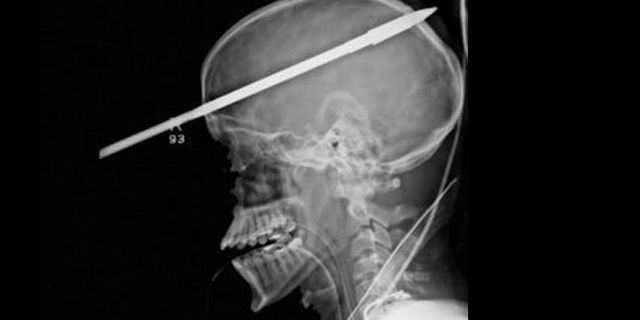

Bild: Jackson Memorial Hospital